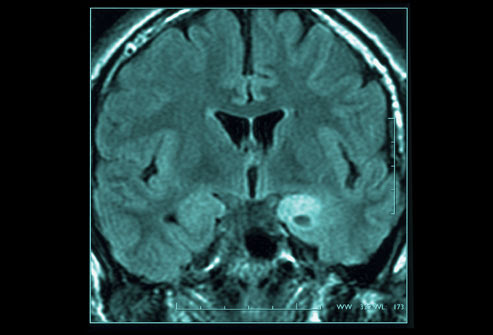

Diagnosis-Brain scan

Change in the structure of your brain, bleeding, or masses can be identical....to diagnose..